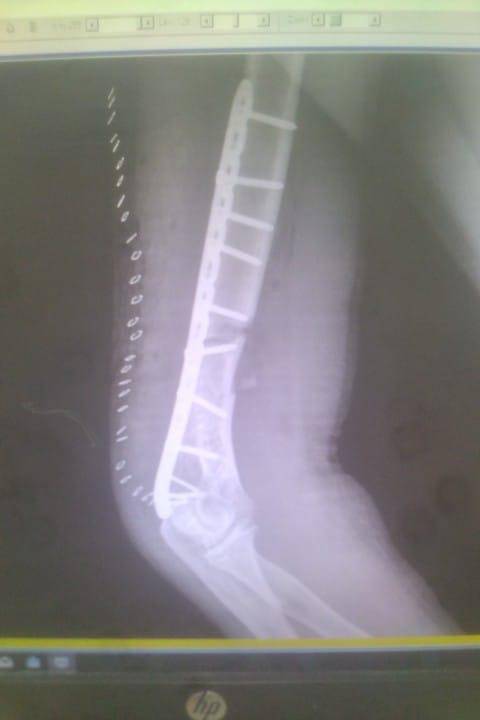

- إجراء عمليات جراحية معقدة و دقيقة في مجال العظام و المفاصل و الكسور و الإصابات ، رغم الضغط الكبير على المستشفى و أعداد المراجعين الكبيرة.

- تطبيق تقنيات جراحية حديثة و متقدمة، و ذلك في ظل التحديات التي يواجهها الفريق بسبب أعداد المرضى و المراجعين الكبيرة.